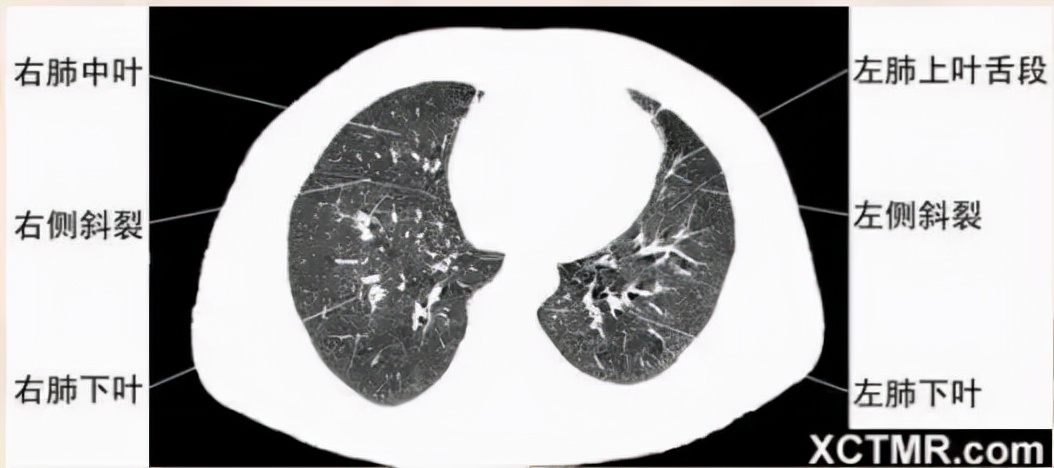

右中叶支气管层面